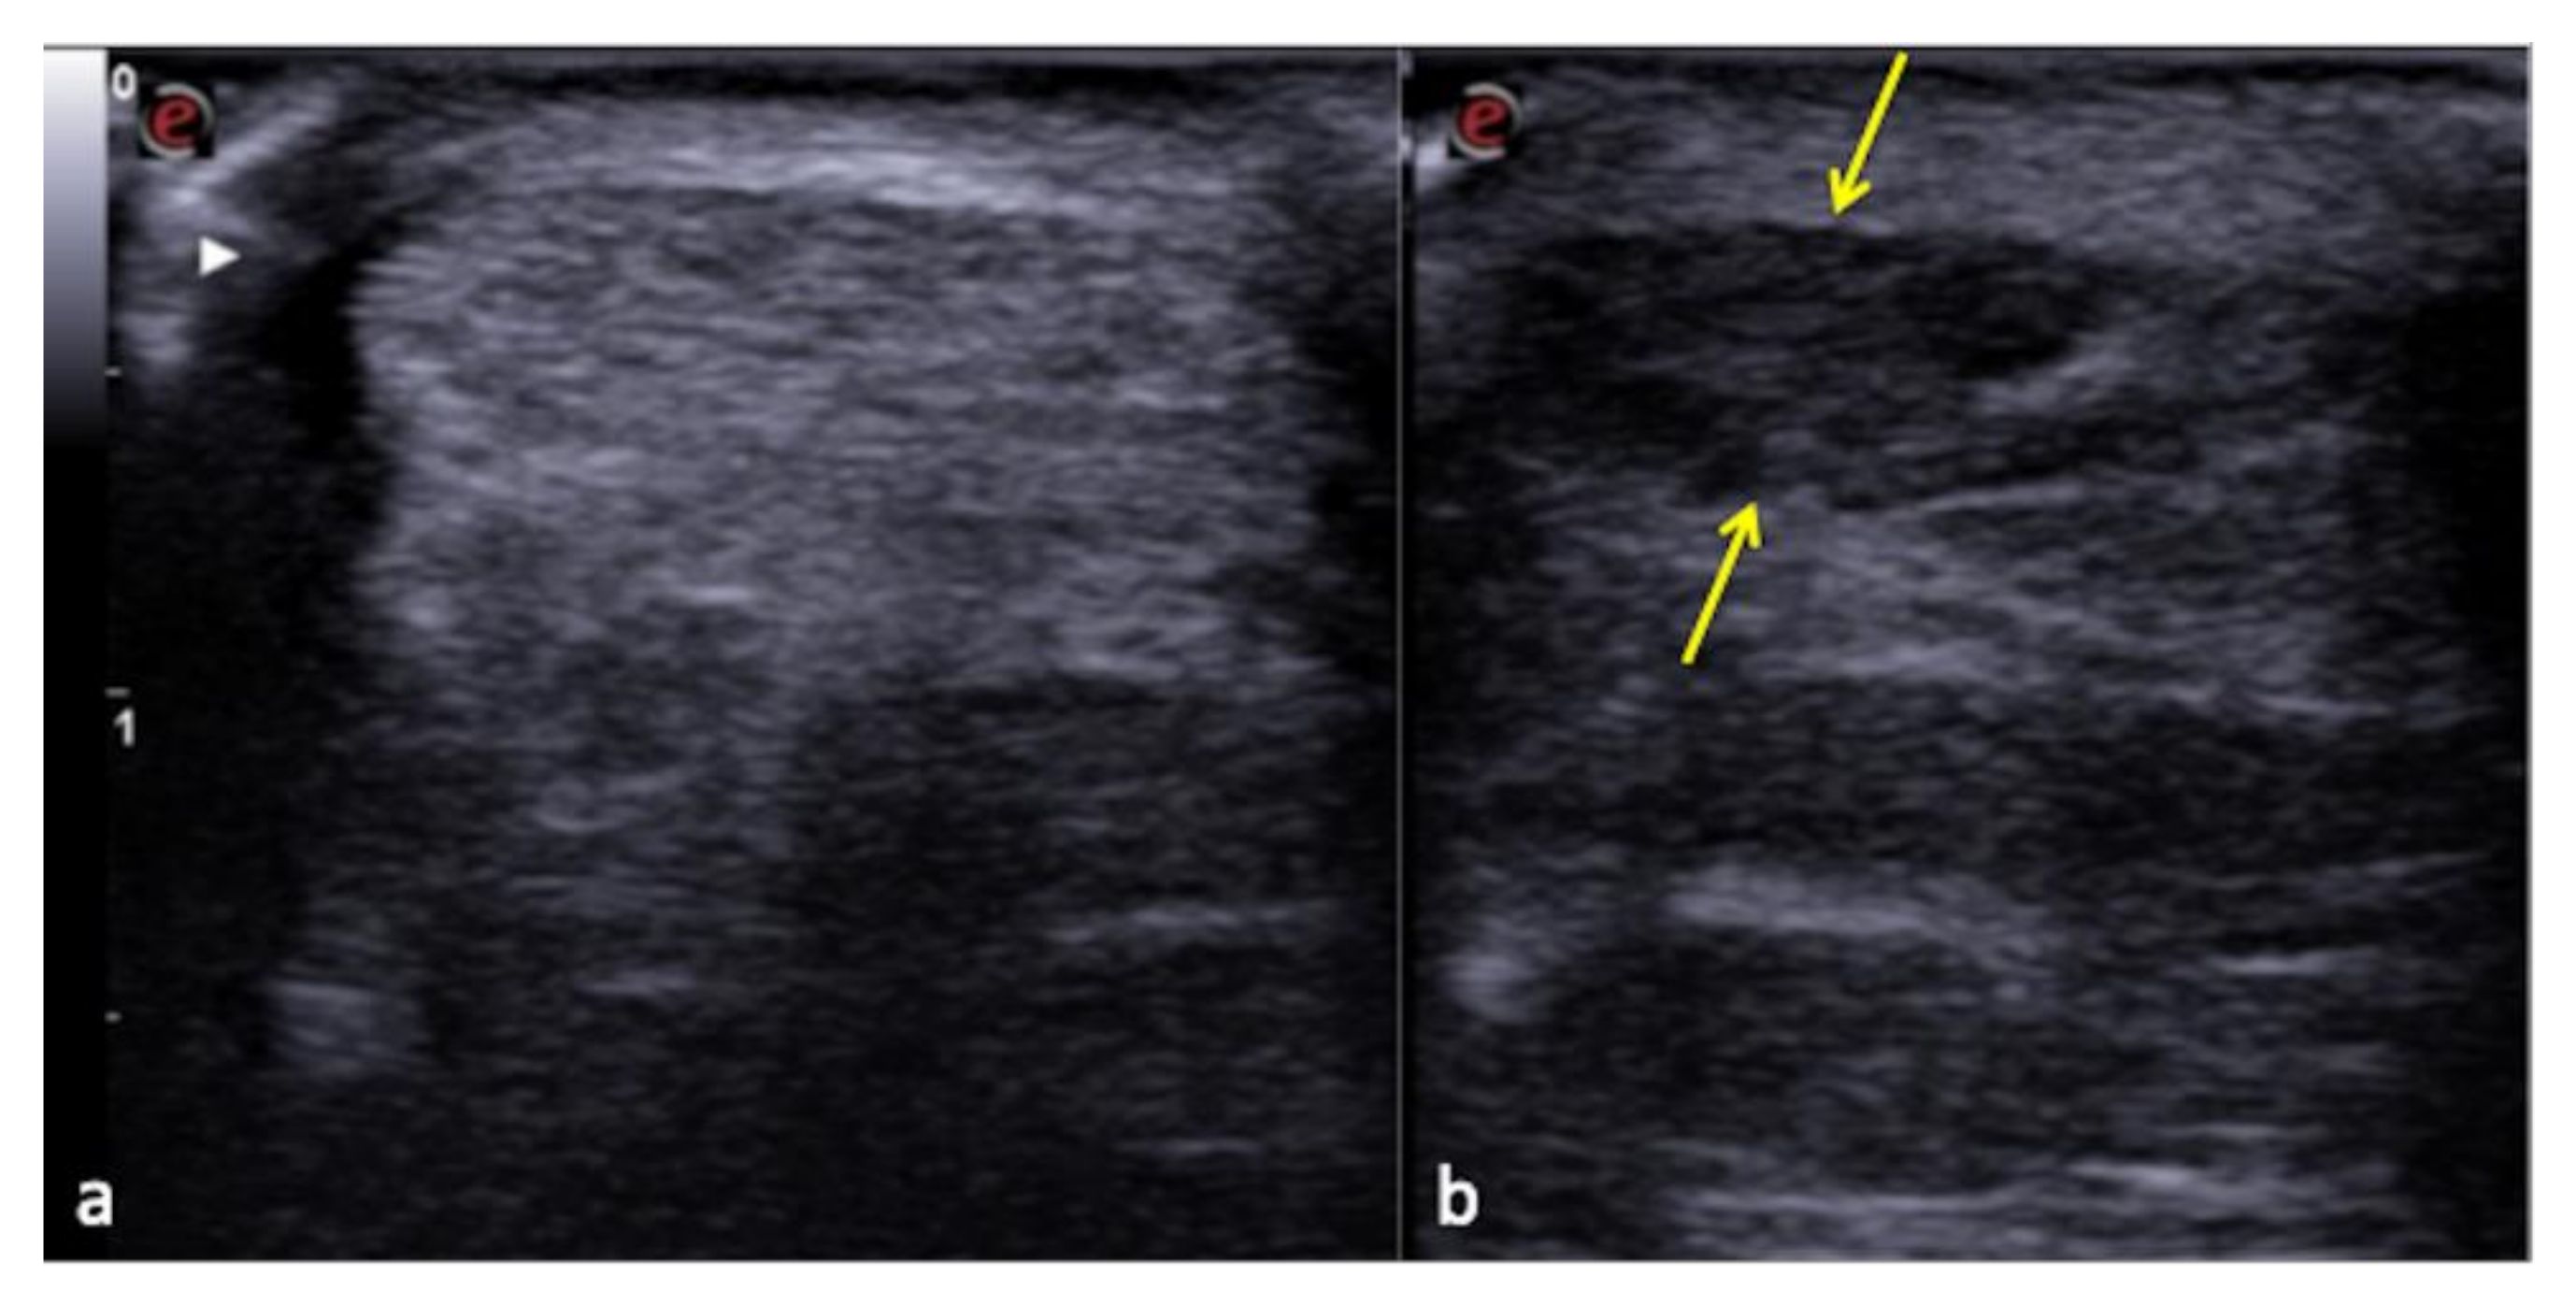

3.2. Chest Artifacts with No Clinical Context

3.3. US-Setting Errors